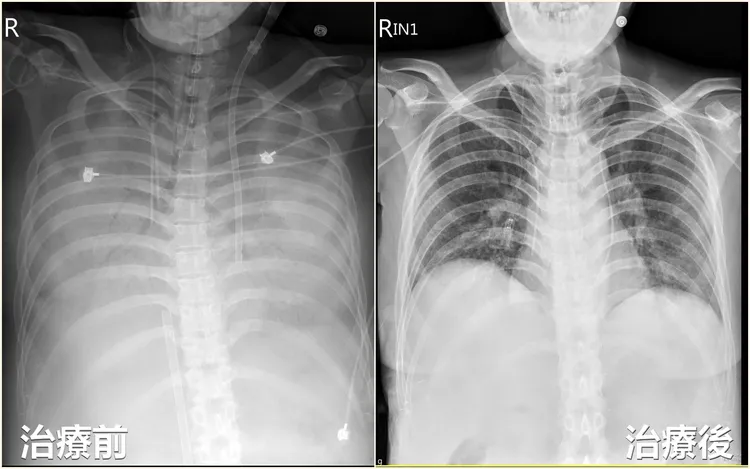

患者因不明原因感染,造成嚴重胸腔及腹腔膿瘍,肺部X光甚至「整片白」。亞大附醫提供

劉殷佐表示,患者雖然勉強維持生命徵象,但腹腔內的膿瘍範圍仍不斷擴大,並從腹部往上延伸,最後連肺臟都失守,胸部X光檢查發現雙側肋膜嚴重積水,「影像上完全看不到肺葉形狀」,只能看到明顯肋骨,評估後決定再放置胸管引流膿瘍,同時採用支氣管鏡灌洗肺泡(俗稱「洗肺」),並做氣切減少呼吸負擔。